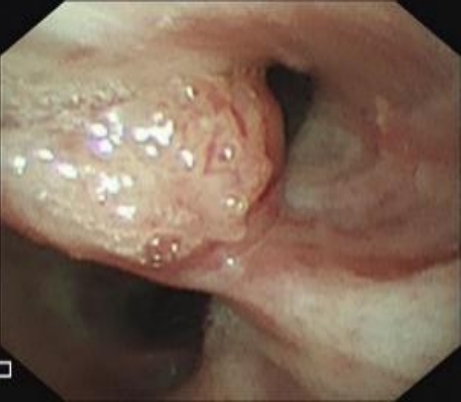

• 获得性免疫缺陷综合征合并马尔尼菲篮状菌导致肠道感染的内镜下表现(附6例报告)

2026, 32(3):84-88. DOI: 10.12235/E20250461

摘要 (32) HTML (27) PDF 3.50 M (26) 评论 (0) 收藏

摘要:目的 探讨获得性免疫缺陷综合征(AIDS)合并马尔尼菲篮状菌(TM)感染导致肠道感染的内镜下特征。方法 回顾性分析2022年11月-2024年10月于该院确诊为AIDS合并TM感染导致肠道感染的6例患者的临床资料。包括:临床症状、实验室检查、影像学检查、内镜检查和病理检查等。结果 6例患者中,男5例,女1例;发病年龄26~67岁;AIDS合并TM感染导致肠道感染患者的临床表现为:腹泻、腹痛、腹胀和恶心呕吐。其中,2例有消化道出血表现。实验室检查:6例患者外周血白细胞计数为(1.37~4.49)×109/L,血红蛋白计数为(67~99)g/L;CD4+T淋巴细胞为(1~52)个/μL,CD8+ T淋巴细胞为(61~321)个/μL,CD4+T淋巴细胞/CD8+T淋巴细胞比值为(0.01~0.18)。6例患者均行HIV RNA检测。其中,5例HIV RNA阳性。血培养:可见丝状真菌,报告显示为TM。影像学检查:6例患者CT结果可见肠系膜及腹膜后多发淋巴结肿大。内镜检查:6例患者内镜下均可见肠道病变。其中,十二指肠糜烂溃疡2例,结肠多发糜烂溃疡4例。病理检查:6例患者幽门螺杆菌(Hp)结果均为阴性,黏膜下可见成簇的小球形真菌孢子,符合TM感染;特殊染色:PAS(+),六胺银染色(+)。结论 当AIDS晚期患者出现消化道症状时,应警惕TM感染,病变部位常见于全结肠和直肠,亦可累及十二指肠,内镜下表现多为溃疡、糜烂和隆起性病变,形态表现无特异性;及时行胃肠镜检查、病理活检、特殊染色和免疫组化是确诊的关键。